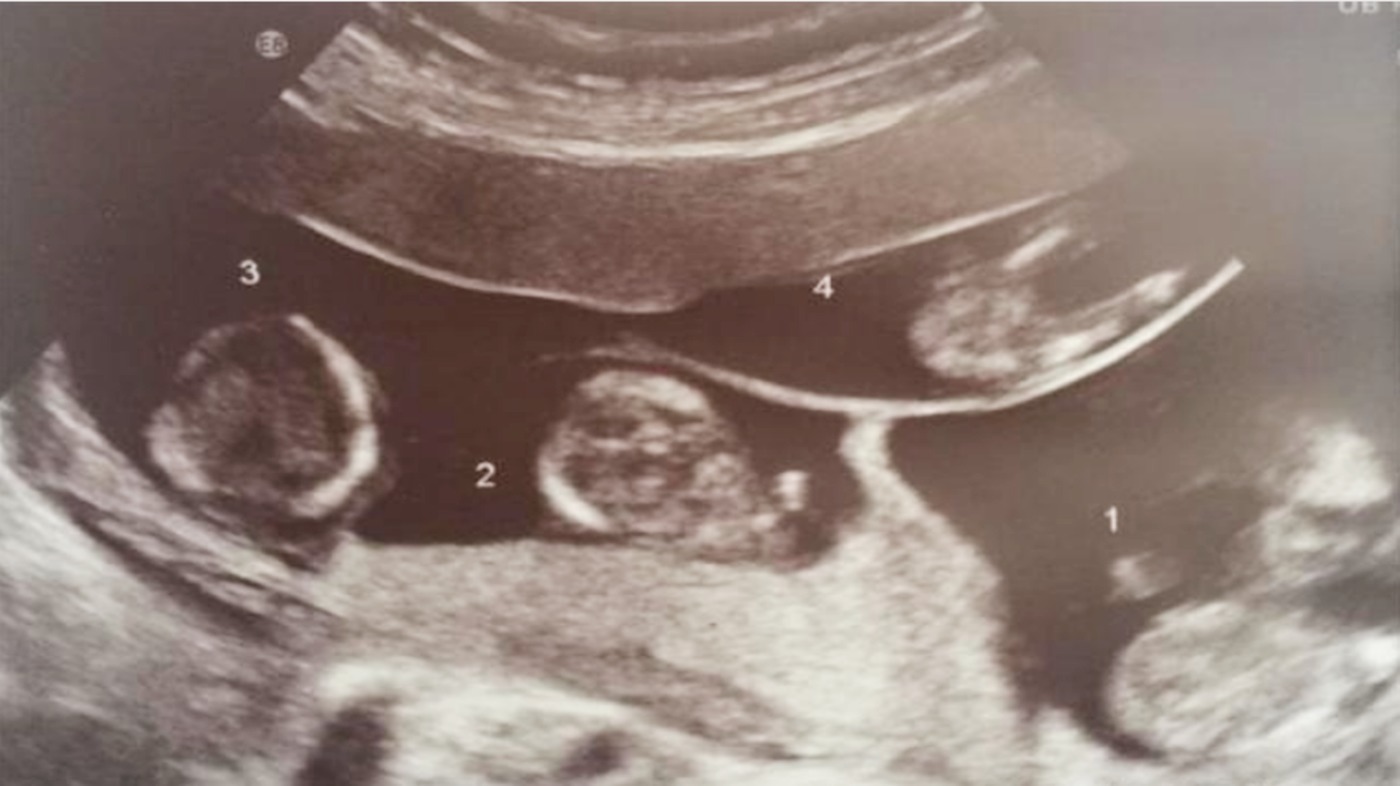

文/贝贝豆(原创文章,欢迎个人转载分享)每当走在路上看到双胞胎时,相信很多的准妈妈都会特别的羡慕,想着也能生一对双胞胎,该有多好呀!不过也有很多准妈妈发现,有些小孩子一眼就可以看出他们是双胞胎,有些长相却完全不同。这是因为双胞胎也是分异卵和同卵哦。妈妈异卵四胞胎,诞下双儿双女,网友:“异卵四生,太幸运了!”国外有一对夫妻,在备孕三年之久后,终于迎来了夫妻俩共同的宝宝。在高兴之后,他们发现竟然怀的是4胞胎。虽然孕期孕妈并不好受,连医生都建议减胎,但是孕妈想着少一个孩子都心痛,坚持要把每一个孩子都生下来。

孕妈的付出有了回报,4个孩子都健康的出生了,双儿双女,这让准爸妈都非常的高兴。等他们出院回家一看,4个娃娃竟然是异卵四生,长得完全不一样,让医生吃惊不已。

要相信,现在的科学这么发达,怀上4胞胎的几率也是可能的。但如果是自然受孕还是异卵4胞胎,这就属于罕见的事情了,这种几率也就只有1/70万,而这很小的概念让这对国外的爹妈给赶上了,连网友都说“异卵四生,太幸运了!”